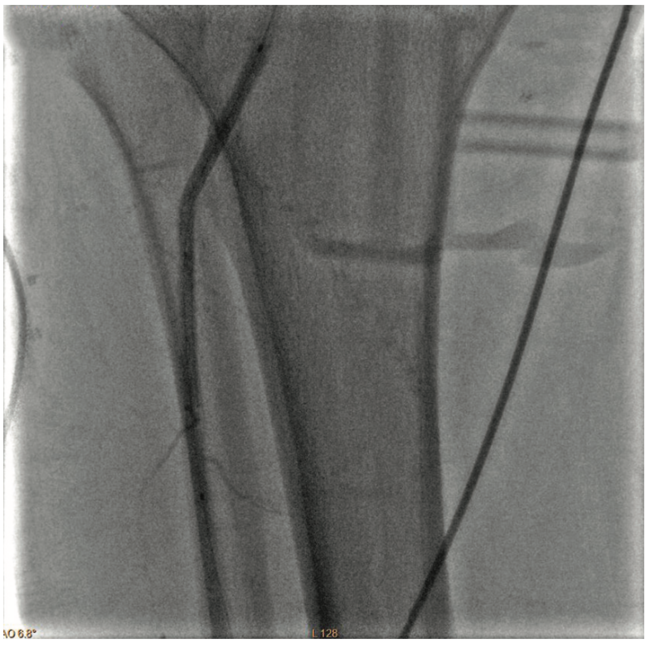

The most significant stenoses were in the popliteal artery and below the knee (BTK) (Figure 1):

• Popliteal: 90% stenosis

• Anterior tibial (AT): 99% subtotal occlusion

• Proximal tibial peroneal trunk (TPT): 80% stenosis

• Posterior tibial (PT) artery: 100% occlusion

Inflow in the popliteal was optimized with plain balloon angioplasty (POBA) prior to addressing the BTK lesions (Figure 2). A 3 mm x 120 mm Serranator PTA Serration Balloon Catheter (Cagent Vascular) was utilized with serial overlapping inflations to treat the anterior tibial artery. The Serranator was used distal to proximal with max inflation at 12 atmospheres (atm) for two minutes (Figures 3-4). A 3 mm x 80 mm Serranator balloon was then used in a similar manner to treat the TPT, with a maximum inflation of 8 atm for two minutes. Following Serranator use, significant lumen gain and improved flow was observed, with 0% stenosis and no dissection, perforation, or recoil noted (Figure 5).